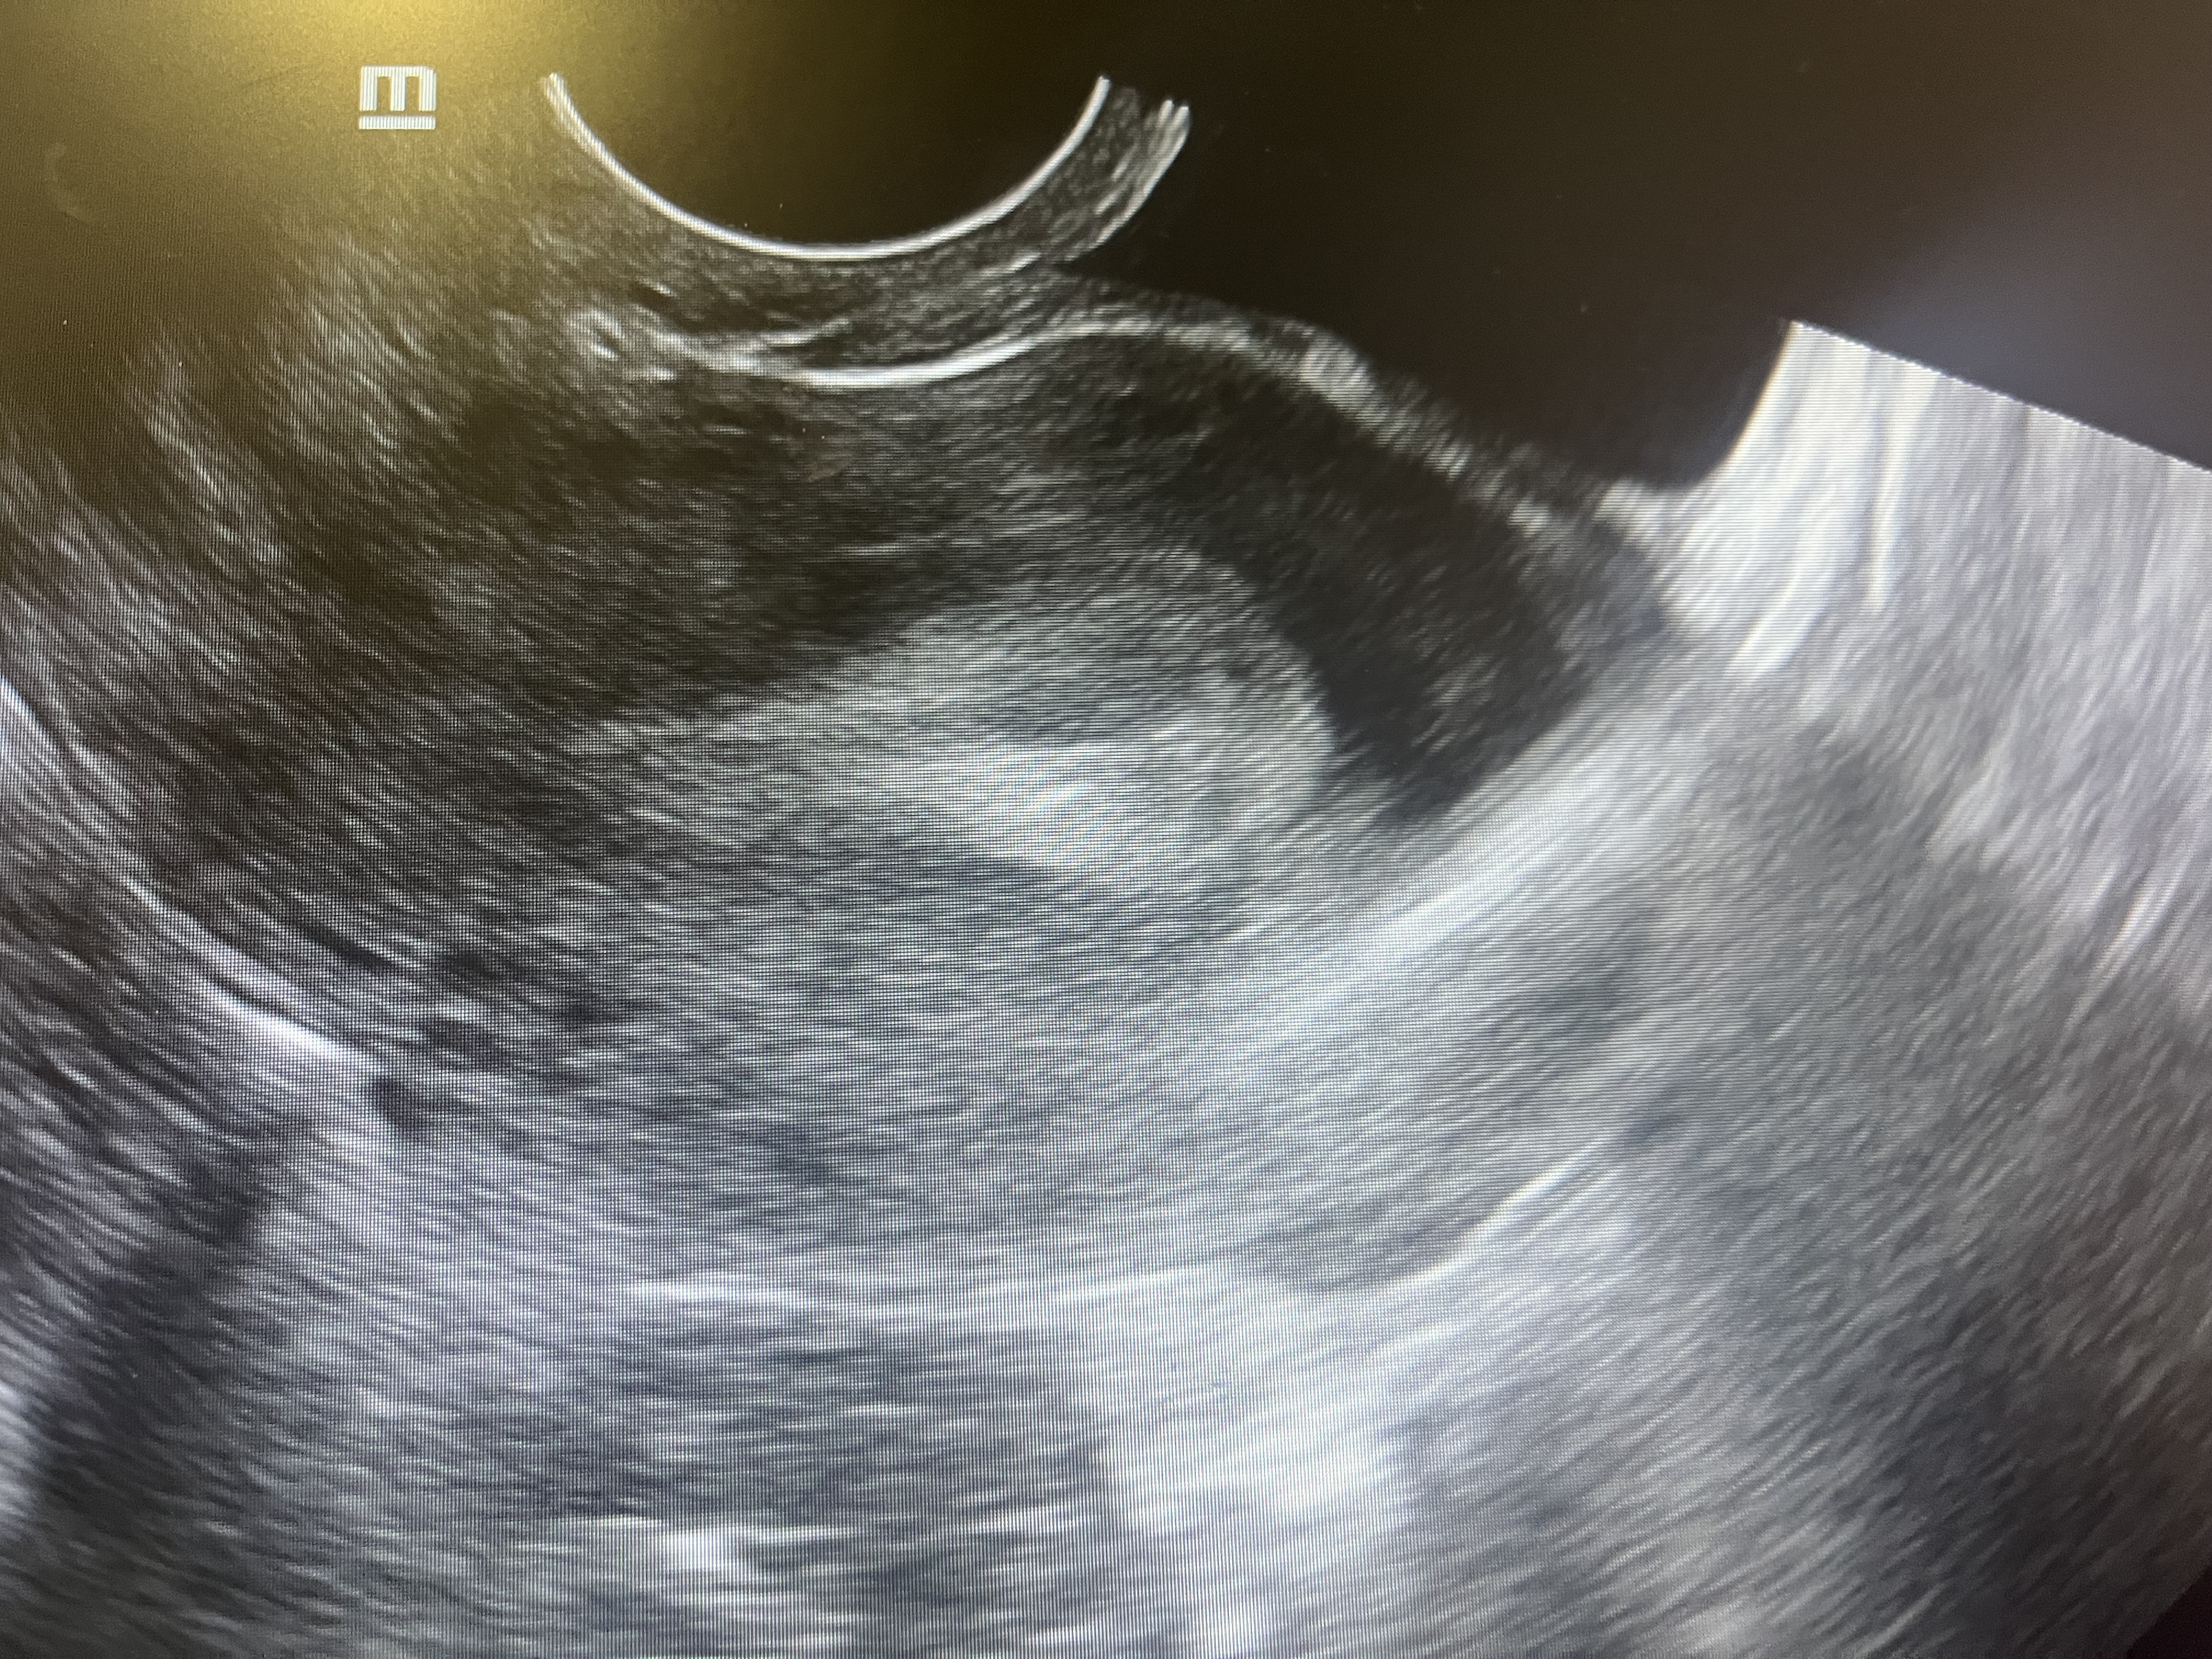

УЗИ, мультифолликулярные яичники

Планирую, жалобы на тянущие боли внизу живота, 22 ДЦ, тесты отрицательные, овуляцию она не увидела, сказала что мелкие фолликулы и эндометрий 14мм, и видит что то в полости, но не думает что это плодное яйцо,поставили Мульти.Ф.Яичники, девочки гляньте, так переживаю, в этом месяце новый здоровый партнер, до этого ни разу не говорили про это диагноз.

Limonchelka, сходила на другое узи, овуляция была в левом яичнике, ЖТ на месте .

Диагноз не подтвердился.